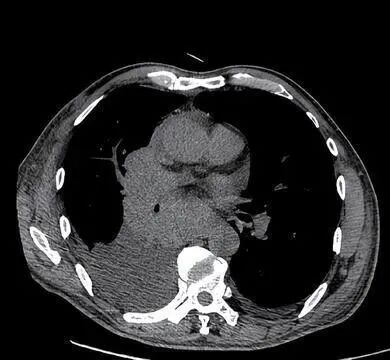

59岁患者,男,干部,吸烟史30年,平时体检胸片,一直未见异常。1年前因咳嗽半月到医院查胸部CT,考虑肺门占位性病变。直接行纤支镜检查,病理确诊小细胞肺癌。

行放化疗治疗,病情曾短期控制,但仍在确诊5月左右死亡,生命最后阶段因为肿瘤压迫大气道、胸腔积液限制膈肌运动,呼吸困难躺不倒特别痛苦。